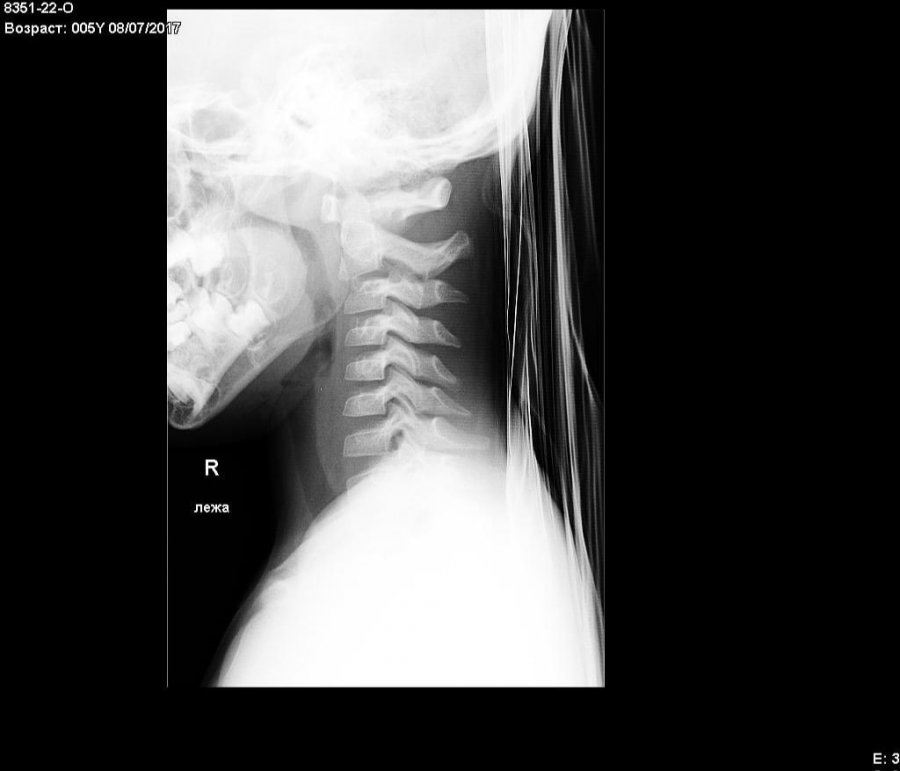

В приемное отделение хирургического корпуса Каширской ЦРБ поступил пятилетний ребенок с жалобами на сонливость, головную боль, тошноту, неоднократную рвоту, боли в шее и животе. Как сообщили в учреждении здравоохранения округа, все эти симптомы появились у мальчика после падения на улице. В больнице осмотр ребенка провели травматолог, хирург, невролог и анестезиолог-реаниматолог. Был установлен предварительный диагноз: сотрясение головного мозга, подвывих второго шейного позвонка, ушиб мягких тканей лба, передней брюшной стенки. По словам дежурного врача травматолога Максима Демчева, пятилетний пациент поступил в состоянии средней степени тяжести. При внешнем осмотре в области лба была выявлена слабая отечность мягких тканей, при пальпации – боль. Видимых изменений шейного отдела позвоночника не было, однако при рентгене выявлено смещение второго шейного позвонка впереди.